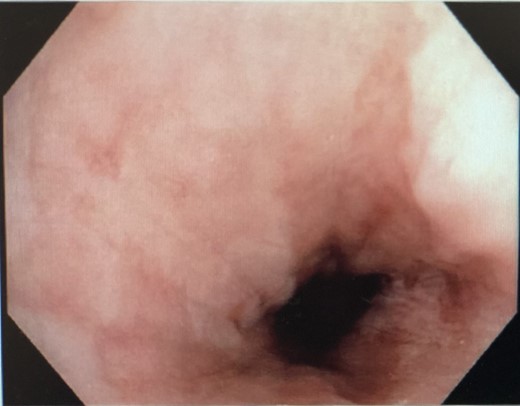

Nasojejunostomy tube was inserted and feeds were commenced. Interval gastroscopy in 2weeks revealed superficial sloughing of esophagus from 27 to 34 cm consistent with partial thickness esophageal necrosis (Fig. 7). Clear fluids were commenced and gradually upgraded to full diet over the course of 6 weeks. Follow-up gastroscopy at 9 weeks showed completely healed mucosa (Fig. 8).

Interval endoscopy at 2 weeks showing signs of healing (Superficial slough at the area of partial necrosis).